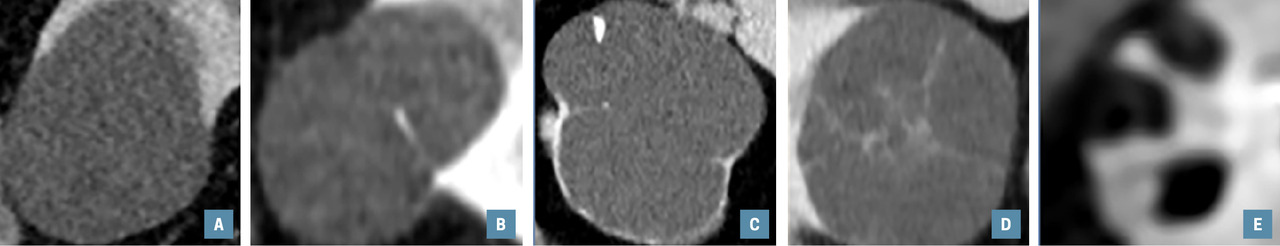

Classification Bosniak en 5 types :

– I, II, IIF, III et IV avec un pourcentage respectif de malignité estimé à < 1 %, 9 %, 18 %, 51 % et 86 % sur séries chirurgicales, le taux de malignité serait plus faible pour les catégories ≤ IIF sur les cohortes de suivi radiologique ;4

– déterminée sur TDM ou IRM d’après l’épaisseur de la paroi, d’éventuels septa, calcifications et surtout en recherchant une prise de contraste murale ou septale (tableau ) ;

– distinguer les I et IV est relativement aisé, plus difficile pour les catégories II, IIF et III (moins bonne concordance inter-observateur).